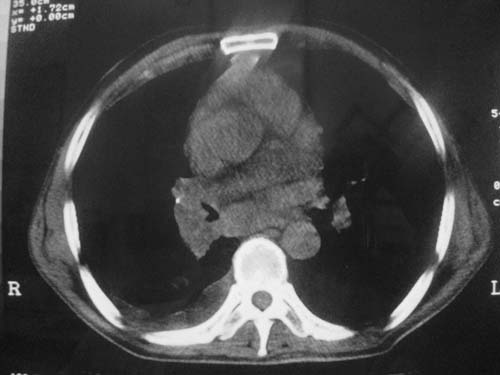

以下是引用科室第一人在2010-3-25 20:30:00的发言:[br]1:纵膈肿瘤性病变,恶性胸腺瘤可能性大伴纵膈右肺门淋巴结转移,右侧胸腔积液。[br]2:右侧肺门肿瘤性病变,纵膈淋巴结转移,右侧胸腔积液。右下叶转移。

以下是引用子期在2010-3-25 21:00:00的发言:[br]先考虑右中央型肺癌伴转移。

以下是引用江广1996在2010-3-25 22:49:00的发言:[br]通常肺癌向纵隔转移多见,纵隔肿瘤向肺内转移少见(有的表现为向肺内侵润)。本例以一元论考虑:右中心型肺癌并纵隔淋巴等多处转移。[br][br][本贴已被 江广1996 于 2010-3-25 22:50:07 修改过]

以下是引用yangyudong333在2010-3-26 6:43:00的发言:[br]“冰冻纵膈”,考虑纵膈淋巴瘤伴肺内及胸膜侵润。